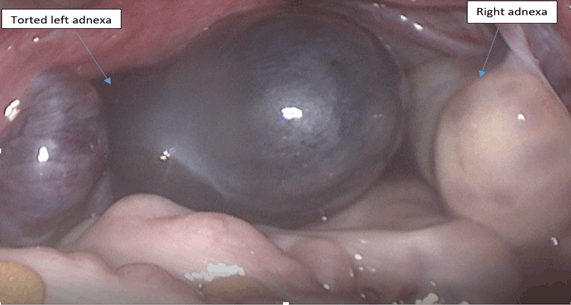

An abdominal-pelvic ultrasound revealed an enlarged left ovary, 20.9 cm3 volume with no evidence of blood flow on Doppler studies favoring a diagnosis of ovarian torsion (Figure 1). She underwent an emergency laparoscopy where the left adnexa were found to be twisted and dark (Figure 2). The right ovary was examined during the surgery and found to be normal. The left adnexa was detorted (Figure 3) but oophoropexy was not performed. However, on checking of the perfusion to the left ovary, it was found to be intact with fresh bleeding visible and change of color of the adnexal tissue to pink. A small incision on the ovary did not reveal any cyst or mass. The surgery was completed with no complications. Postoperative symptoms were pain on the port sites with mild nausea that was managed well with oral analgesics and antiemetics. The patient recovered well from the surgery and was allowed home on the second postoperative day. On follow-up after two weeks the patients had no symptoms and revered fully.

Figure 2: Intraoperative view of the adnexal torsion before detorsion.